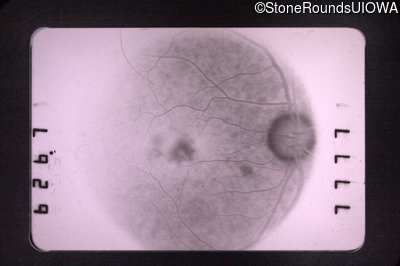

Fluorescein Angiography - Right - 20/30

Exemplar